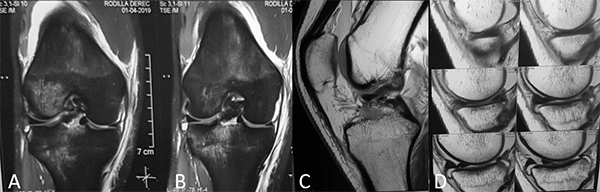

Se solicitó Rx, donde se constató fractura de espina tibial grado 3 (fig. 1), además, una tomografía axial computada (fig. 2), aportando un patrón conminuto del fragmento y RM, donde se evidenció, además de la fractura de espina tibial, una lesión en asa de balde del menisco interno (fig. 3).

Figura 3: Resonancia magnética. A-B) Cortes coronales: distensión del ligamento colateral medial, lesión en asa de balde del menisco interno, fractura avulsión de espina tibial, “bone bruise” en compartimento lateral. C-D) Cortes sagitales: avulsión de espina tibial grado 3 y tercio posterior del menisco interno flipeado hacia anterior.